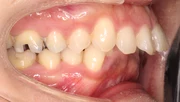

難しいケース2.上顎前突(出っ歯)

上の前歯や上顎が大きく前にでているかみ合わせ。口元が出ていて、出っ歯を治したいという希望の患者さま。23ヶ月という治療期間を経てかみ合わせと口元が改善しました。